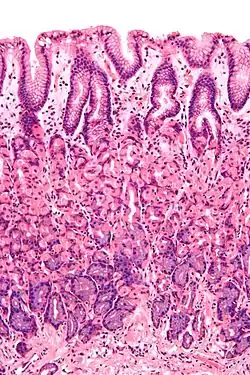

Epithelial cells line body surfaces, and are described according to their shape, with three principal shapes: squamous, columnar, and cuboidal.

Epithelium can be arranged in a single layer of cells described as "simple", or more than one layer, described as "stratified". By layer, epithelium is classed as either simple epithelium, only one cell thick (unilayered) or stratified epithelium as stratified squamous epithelium, stratified cuboidal epithelium, and stratified columnar epithelium that are two or more cells thick (multi-layered),[2][3] and both types of layering can be made up of any of the cell shapes.[4] However, when taller simple columnar epithelial cells are viewed in cross section showing several nuclei appearing at different heights, they can be confused with stratified epithelia. This kind of epithelium is therefore described as pseudostratified columnar epithelium.[5]

Mucosa

A mucous membrane or mucosa is a membrane that lines various cavities in the body and covers the surface of internal organs. It consists of one or more layers of epithelial cells overlying a layer of loose connective tissue. It is mostly of endodermal origin and is continuous with the skin at various body openings such as the eyes, ears, inside the nose, inside the mouth, lip, the urethral opening and the anus. Some mucous membranes secrete mucus, a thick protective fluid. The function of the membrane is to stop pathogens and dirt from entering the body and to prevent bodily tissues from becoming dehydrated.